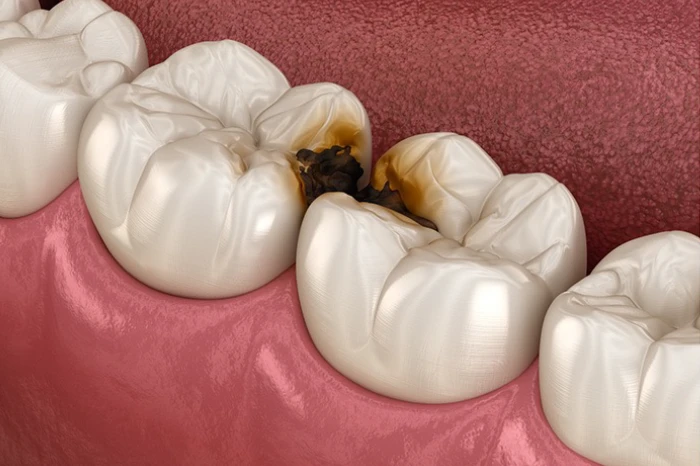

痛みの原因① ヒビからの刺激

前述の通り、歯ぎしり・食いしばりによって歯にヒビ(マイクロクラック)が入ります。

このヒビから「細菌」「冷たいもの」「噛む力」などの刺激が入り込み、象牙細管を通して神経に伝わることで痛みが出ます。

痛みの原因② 虫歯の侵入

さらに注意が必要なのは、ヒビから虫歯菌が侵入することです。

見た目では虫歯がなくても、内部で刺激が神経に届くことで、「原因不明の痛み」として感じることがあります。

虫歯になる?

「歯ぎしりや食いしばりで虫歯になるの?」あまり結びつかないように感じるかもしれません。

しかし実際には、歯ぎしり・食いしばりが虫歯の原因になることはあります。

虫歯になる仕組み

虫歯になる流れを分かりやすく説明すると、以下の通りです。

① 歯ぎしり・食いしばり

歯と歯が強く擦れ合います。

② ヒビ(マイクロクラック)が入る

目に見えない細かい亀裂ができます。

③ 再石灰化が追いつかない

通常は唾液によって修復されますが、寝ている間は唾液が少なく乾燥するため修復されにくいです。

④ 細菌が侵入

ヒビから虫歯菌が入り込みます。

⑤ 虫歯になる